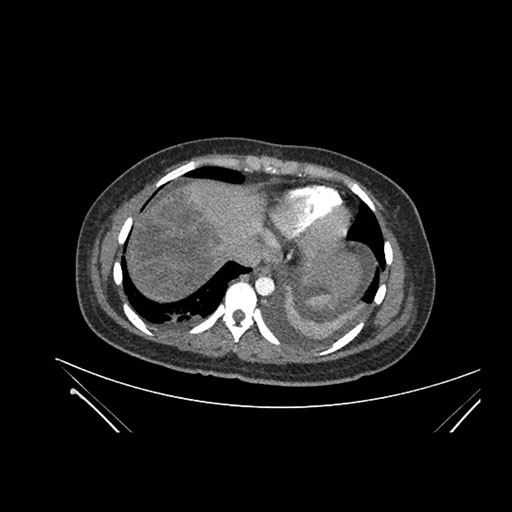

Imaging Analysis

Look through the patient's CT scan to identify any areas of concern for the necessary procedure.

Axial Arterial